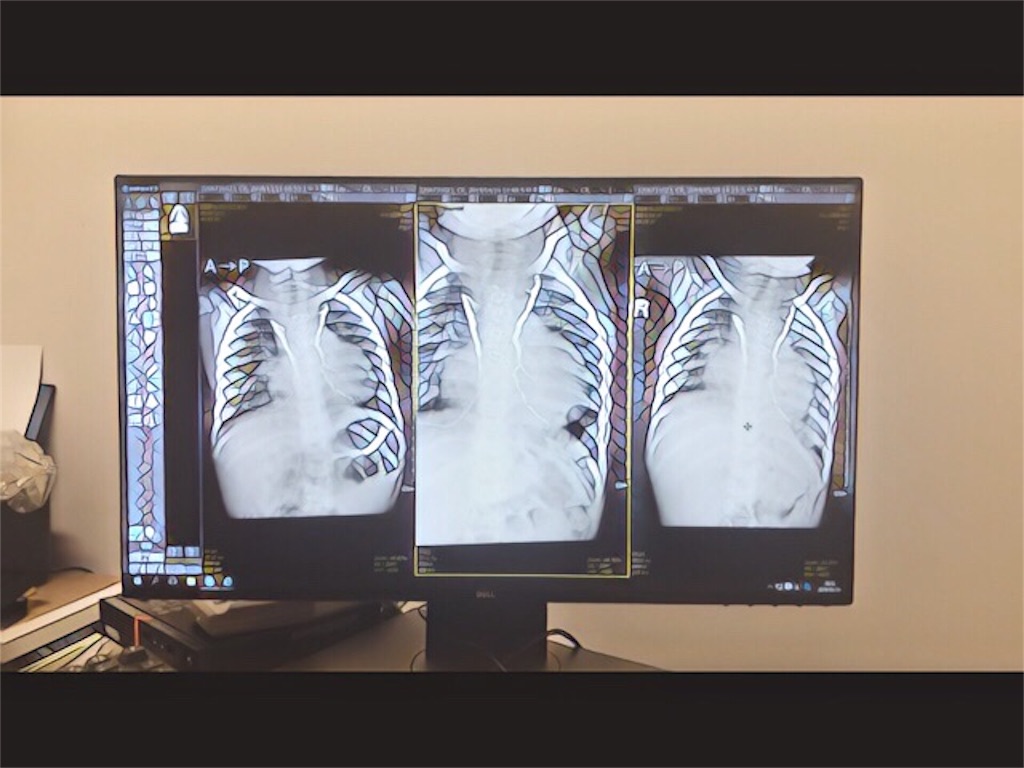

残念ながら半年前のカテーテル検査より全身の酸素化がやや悪化していた。

肺動脈について

- 太さ…前回と同様

- 圧力…やや圧力+(前回は8〜9、今回は10〜11)

- 肺動静脈瘻…肺静脈のSpO2 *3がやや悪化

- 肺体血流比…0.9

新たに判明したこと

- 肺の酸素化の機能が落ちている

- 腸が横隔膜より上にせり上がっており(ヘルニア)、肺を圧迫している(?)

- 静脈〜肺静脈の側副血管*4が出来ている

- 側副血管の一部は心臓の内部に通っている

横隔膜よりせり上がった腸が左肺を押していて、酸素化機能が阻害されている可能性があるそうだ。

昨日の記事で左肺の下部が白っぽいと書いたのは、これが原因だったのか。